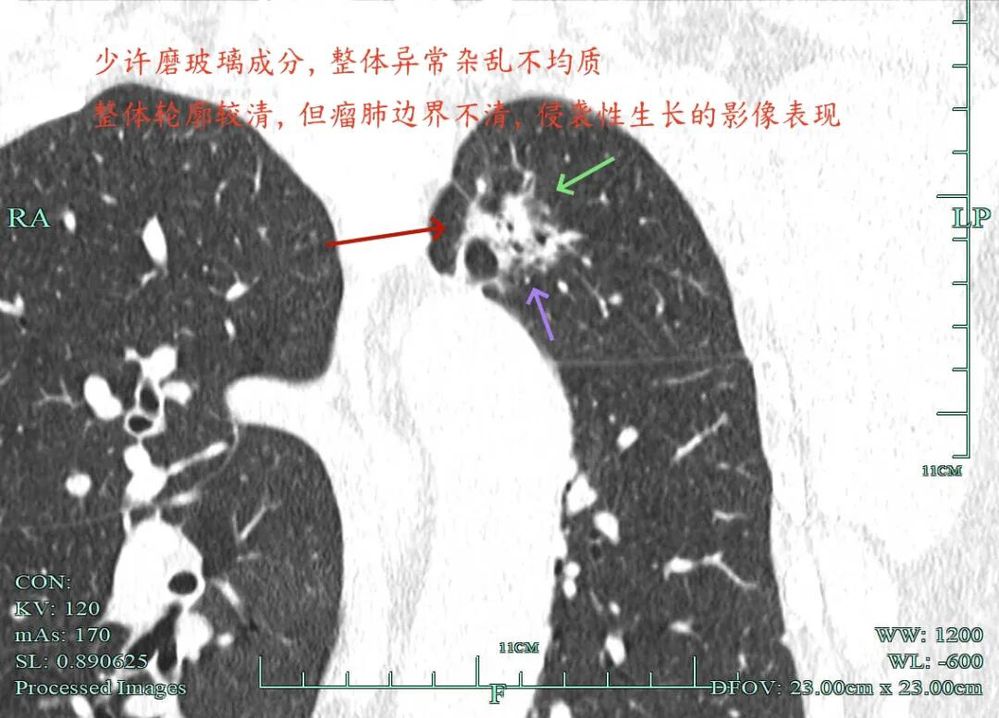

杭州市肿瘤医院影像展示与分析:

右上也有混合密度结节,实性部分缺乏膨胀性与收缩力,磨玻璃成分较淡,也偏糊,但持续存在仍得考虑肿瘤范畴可能性大。

此视角是混合密度,实性为主,贴胸膜近。

左侧主病灶长达三年半时间的随访,当时就是混合密度,整体轮廓较清,随访不好转的话就是要高度警惕恶性的。现在病灶已经明显进展,实性成分增多明显,考虑浸润性腺癌可能性大。肺的粘膜相关B细胞淋巴瘤一般缺乏毛刺征,整体病灶的轮廓与边界会再偏模糊点。但从三年多随访范围增大不多,仍有磨玻璃成分来讲,个人认为已经有转移了的概率可能并高。大概率是中分化浸润性癌可能性大些。右侧病灶也是要考虑浸润性腺癌的,但一是它小些,二是处理要先处理风险更大的一侧,所以右侧病灶拟后续随访叶视其进展再微创干预。

今天这位结友的病理类型稍差于术前的预测,但从其三年多随访情况来看,进展不算大厉害,第10组与第12组淋巴结均阴性的话,还是真早期的可能性还是较大的。后续倾向暂随访观察,可以采取相对稍积极的随访策略,比如两年内4个月复查一次,三到五年内半年复查一次,五年后再年度复查;而且右侧的病灶要在随访进展或身体恢复良好后微创局部楔形切除。期间万一有转移,其实是伪早期的话,则基因检测并全身性治疗。其实今天这种病灶在临床中被判断为炎性的并不少见,尤其是非胸外科医生。因为胸外科的一般相对积极,警惕性高些。在我的公众号上其实也分享过多例这种看着似乎是炎性,但长时间随访不好转,或缓慢进展的病灶其实是浸润性腺癌的一种特殊表现,不少见的。我感觉此类病灶比较主要的临床特征是:1、密度多是混合磨玻璃密度,实性成分较明显,磨玻璃成分较淡,病灶显得密度较为杂乱不均;2、整体形态膨胀性不明显,收缩力不太强;3、灶内支气管通气及显得较为僵硬,血管征不典型,但表面多是不平不规则,较为毛糙,分叶多可见;4、随访或抗炎治疗不好转,进展不快,相对较为缓慢。容易被人以为是慢性炎症。但此时我们要注意几点:1、寻找磨玻璃成分,并观察瘤肺边界,尤其是磨玻璃成分与周围正常肺组织之间的界限是否清楚,清楚的多是恶性;2、靶重建从不同角度观察病灶形态,看病灶与邻近结构的关系,有无推压、破坏或支气管截断等征象;3观察病灶内部通气支气管的形态,扭曲、僵硬不舒展的多容易是恶性病变。总体上,要对“影像看着像慢性炎,但随访持续存在且有磨玻璃成分的”病灶要特别提高警惕,对于靠近边缘部分的,手术创伤不大的,要考虑“开刀带来创伤与随访导致的风险”之间的利弊权衡。我的根本理念仍是:淡化最后病理结果,从风险角度考虑问题!